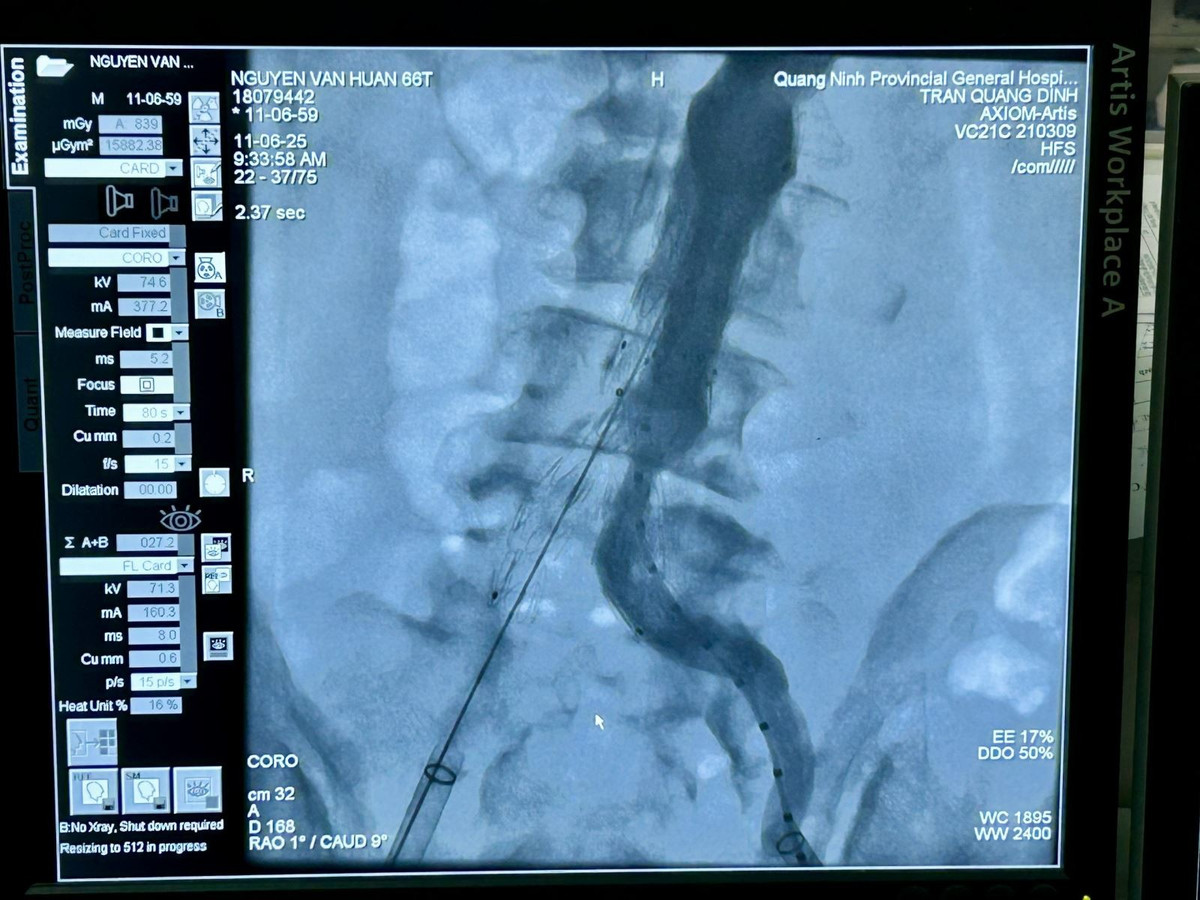

Ca can thiệp do BSCKII Trần Quang Định, Trưởng khoa Phẫu thuật và Can thiệp Tim mạch thực hiện với sự hỗ trợ của chuyên gia. Ê-kíp tiến hành đặt stent graft tại vị trí khối phình động mạch chủ bụng đoạn dưới thận và 2 stent nhánh vào động mạch chậu hai bên.

stent-3.jpg

Ê-kíp can thiệp tiến hành đặt Stent Graft dưới sự hỗ trợ của hệ thống DSA 2 bình diện - Ảnh BVCC

Hình ảnh chụp từ hệ thống DSA cho thấy stent graft đã được đặt đúng vị trí khối phình động mạch - Ảnh BVCC